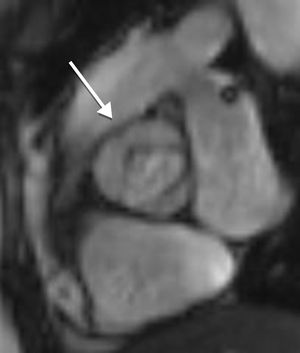

Aortic diameter, corrected for age and body size, is accurate for predicting aortic events, and is the principal risk marker for aortic dissection.1,5 An ascending to descending aortic diameter ratio above 1.5 signifies ascending aorta dilatation if descending aorta diameter is normal. There is another alternative to identifying aortic dilatation that correlates more closely with aortic diameter, because it adjusts aortic dimensions for body surface area (BSA); this is important due to the relatively short stature of patients with TS. This latter method involves estimating the aortic size index (ASI): aortic diameter (at the ascending aorta or at the site with the largest dimension)/BSA. It has been proposed that an ASI ≥2 cm/m2 identifies those who require close monitoring and an ASI ≥2.5 cm/m2 (as in Figure 4) requires aortic surgery to prevent aortic dissection.4,21,24,25

C.2. Persistent left superior vena cavaThe venous return from a persistent left superior vena cava (PLSVC; Figure 5) has a prevalence of around 13%. In approximately 80% to 92% of cases, the PLSVC drains into the right atrium via the coronary sinus, resulting in no hemodynamic consequences. However, in about 10% to 20% of cases, it drains into the left atrium and results in venous blood returning to the left atrium.11,32